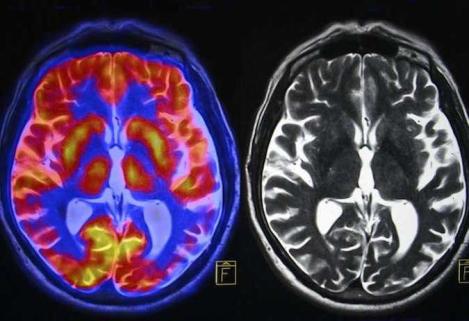

In the doctor’s office she handed it to me. It is carved, mahogany maybe, shining with a burnished gleam. Two globes and the sand an emerald green, already trickling. She shows me the scan, this patch, she says, shows that part of your brain is dead. We think you’ve had a stroke.